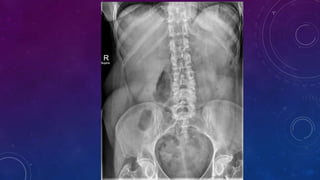

WHERE?

PROSTATIC CALCIFICATION

SPOT 3 ORGANS

WITH

CALCIFICATIONS

Gall stone

Calcific pancreatiits

Penile calcification

?